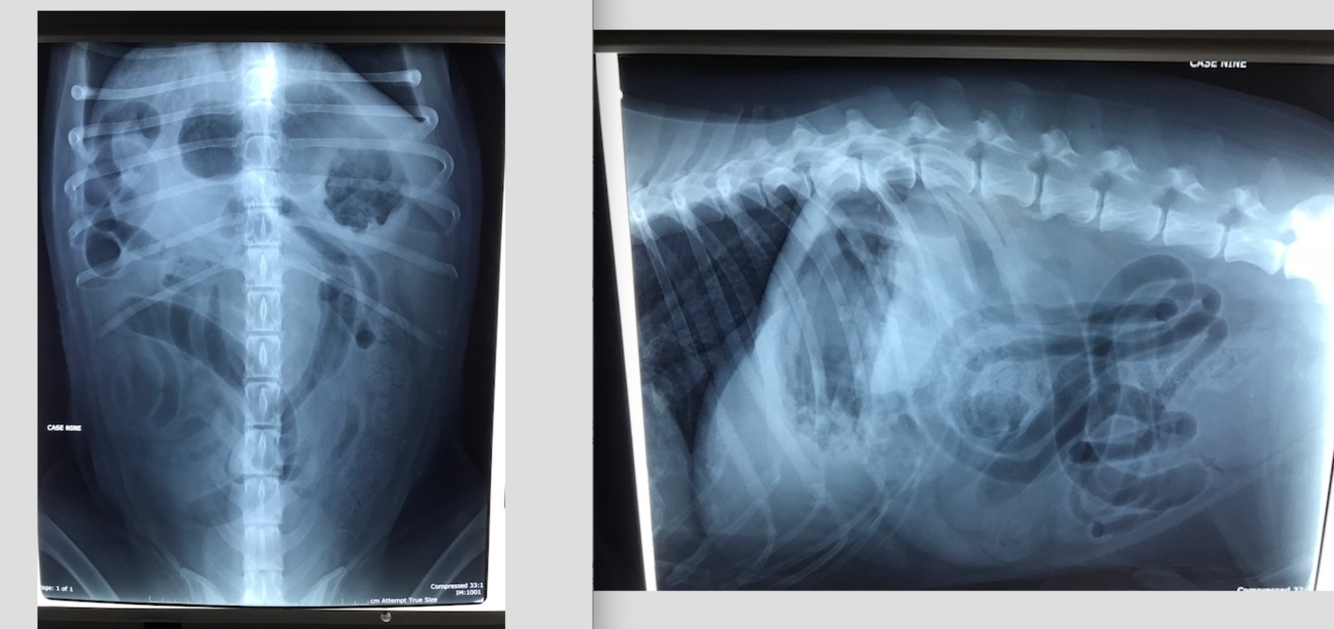

8 yo M Staffy

Previous history of two laparotomies- Owners concerned re: another FB

HR 130 RR 38.6C

No pain on abdo palp

12 yo MN Labradoodle

Acute v+, lethargy, and profound weakness, but concurrent history of chronic vomiting and weight loss

HR 160 with injected MM

panting

Relaxed abdomen– firm area cranio ventrally– mass?? Cannot rule out tail of spleen

Gas filled stomach– rule for distension?

Over distended SI– what is the rule to assess for presence of mechanical SI obstruction?

The over distended SI loop within the mid ventral abdomen containing multiple fragmented gas opacities… what do you think this is most likely to be?

Ventral spondylosis L2-3

What is your plan for Austen